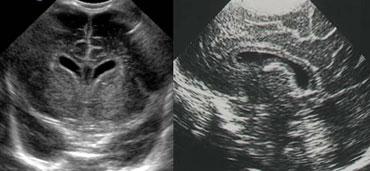

TRÁI: Mặt cắt đứng ngang, mũi tên xanh lá chỉ xuất huyết độ 3. PHẢI: Mặt cắt đứng dọc, mũi tên vàng chỉ nhồi máu tĩnh mạch.

Xuất huyết nội sọ độ 3

Hình bên trái là xuất huyết nội sọ độ 3 lấp đầy não thất bên trái.

Cũng lưu ý vùng tăng âm hình nêm ở phía trên-bên của não thất.

Đây là hình ảnh của một ổ nhồi máu tĩnh mạch nhỏ.

Cùng bệnh nhân như trên.

Hai tuần sau, ổ nhồi máu tĩnh mạch đã tiến triển thành vùng giảm âm với sự hình thành nang.